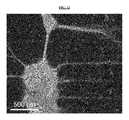

FIG. 10 illustrates non-limiting scanning electron micrograph of the nerve regeneration pathway luminal surface. The image displays the profiled luminal surface corresponding to the profilometry measurement shown inFIG. 4B. The yellow line indicates the path of the surface profiler.